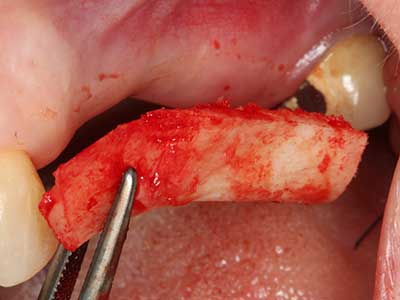

Piezo surgery has additional advantages when harvesting bone blocks. In addition to the high precision with osteotomy described above, the use of the thin saw tips specifically minimizes loss of material. Greater loss of material during harvesting can be expected with the thicker instrument tips, particularly when using Lindemann drills (Lakshmiganthan, Gokulanathan et al. 2012). The basal separation, which is necessary particularly for retromolar block transplants, is simplified by specially designed rectangular saws, with the result that piezo surgery is viewed as a precise, simple and safe procedure for harvesting retromolar bone blocks (Happe 2007) (Fig. 1-12).